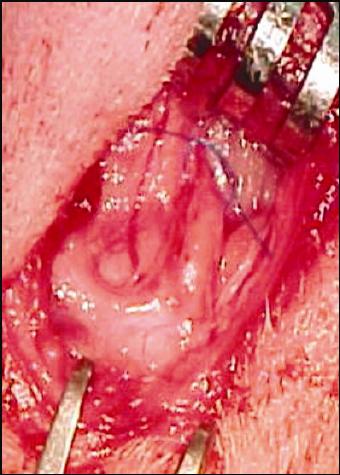

(Fig.1).

FIGURA 1: Animal na mesa operatória para cirurgia em nervo facial esquerdo.